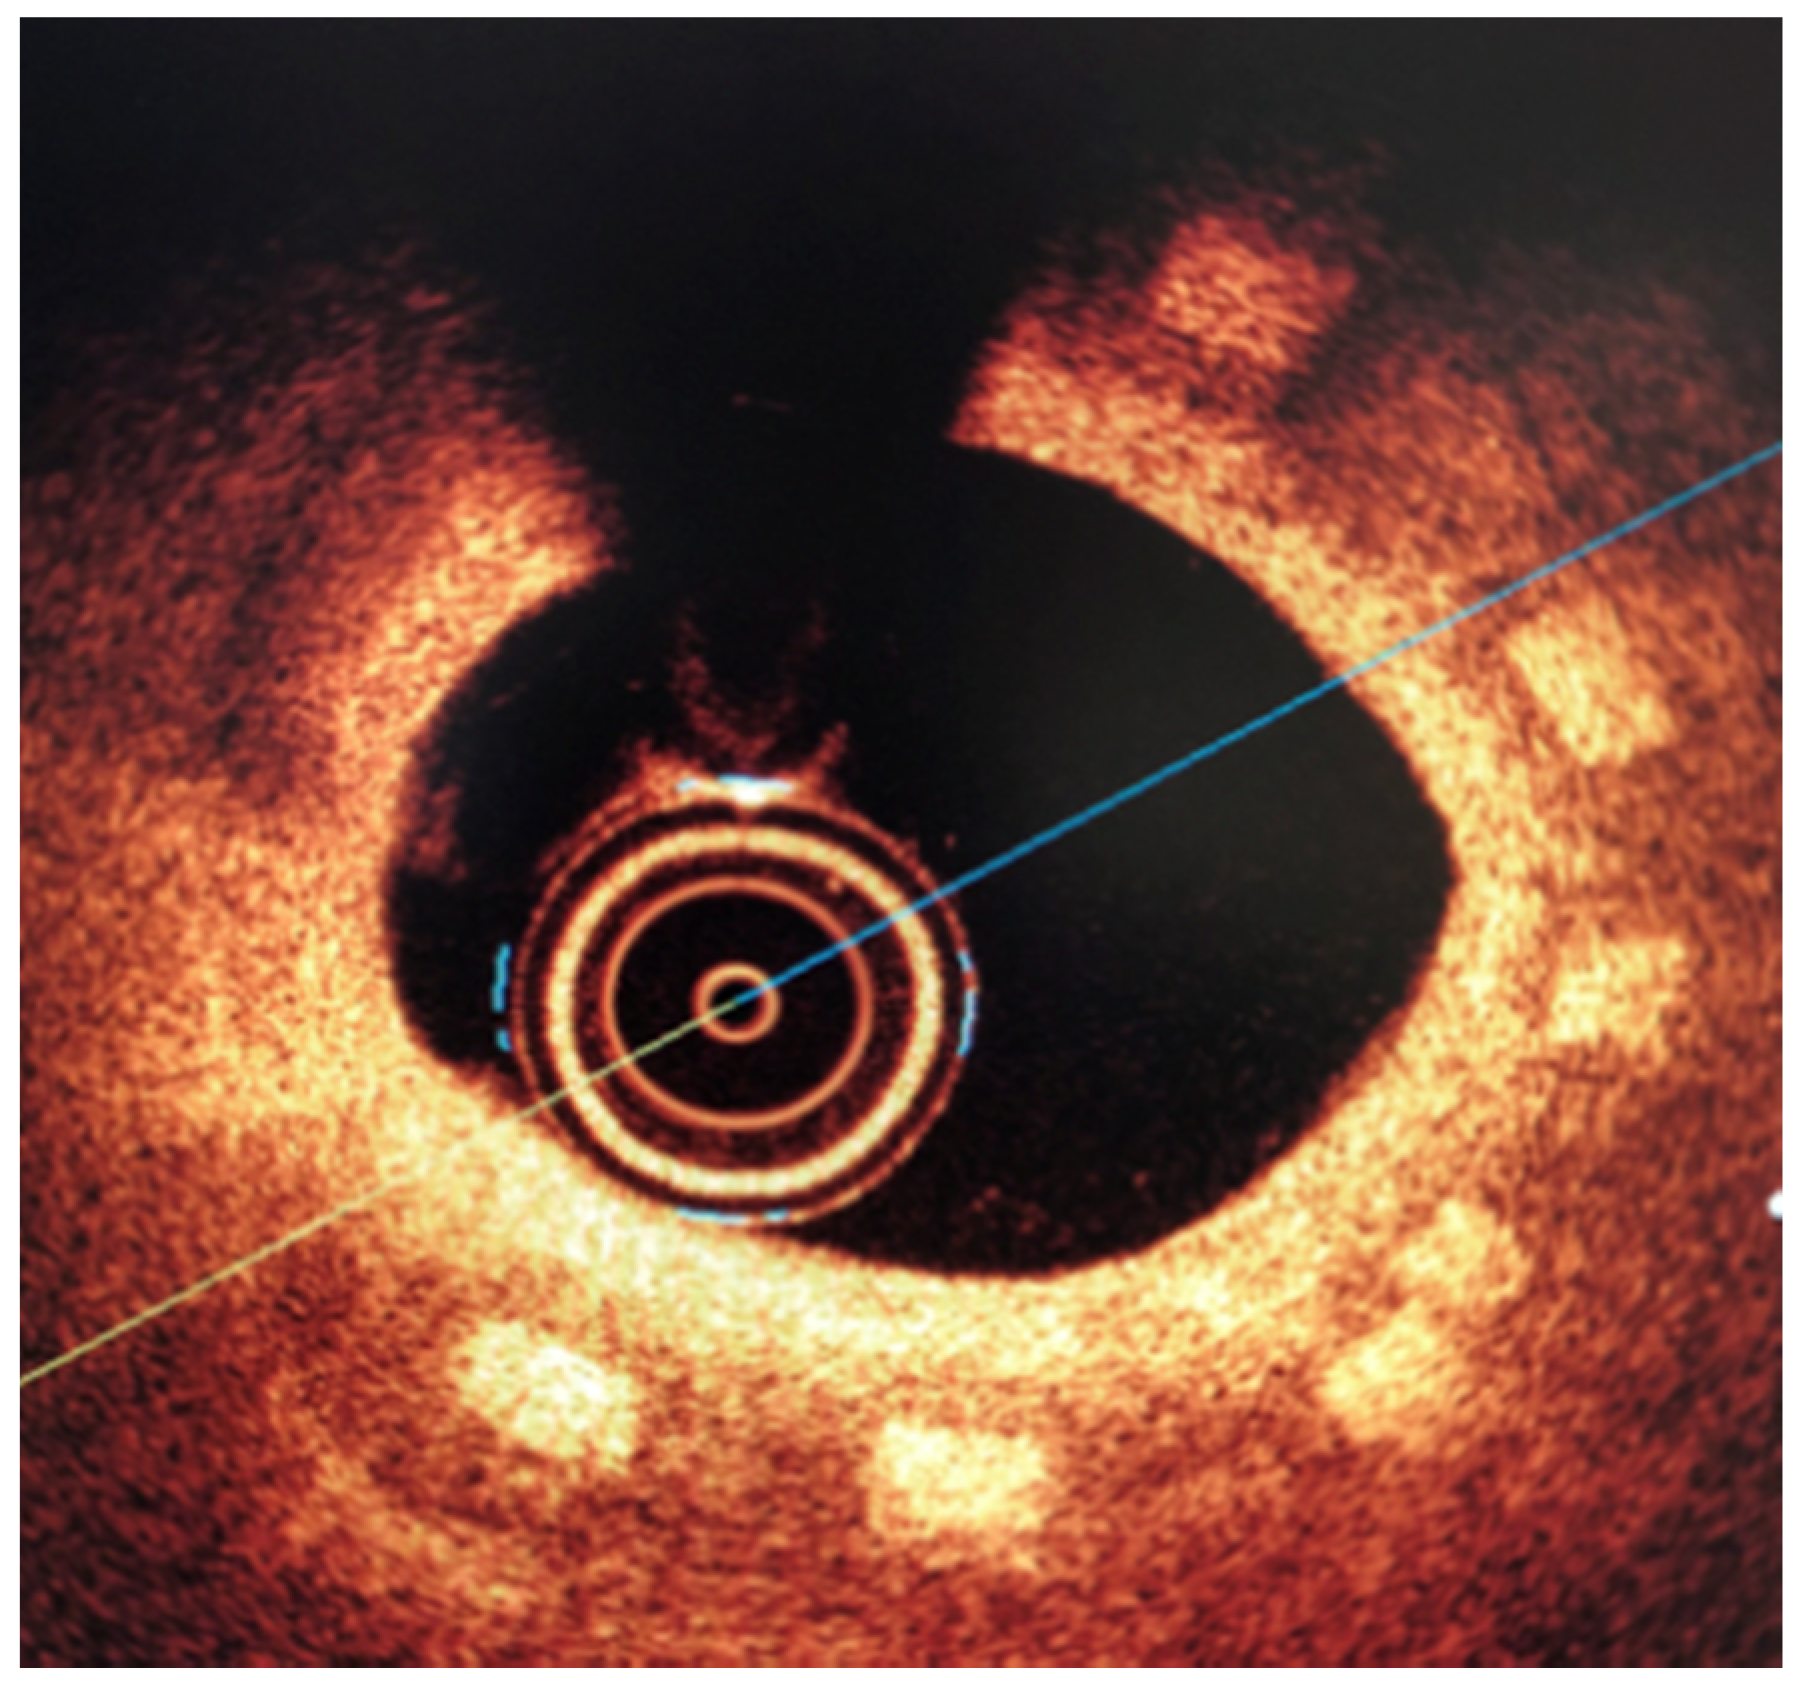

3.2. Biological Response

All three stents were implanted successfully. In coronary angiography stents showed enough radial force to support overstretched vessel (Figure 13). The OCT has shown good stent apposition and the analysis has shown lumen enlargement post implantation 24% as shown in Figure 13c. At 28-day follow-up, all stents were covered with neointima, and struts embedded. Interestingly the signs of material hydrolysis were observed thus proving the polymer amorphic properties (Figure 14).

Figure 14.

Optical coherence tomography at 28 days follow-up show optimal vascular response and stent geometry. Stent struts show blurred image, a sign of early hydrolysis (rectangle).

The results presented in the mathematical modeling has shown sufficient radial force, inflate, expand and implant a tested stents in the coronary vessel. This was validated by mechanical radial force tests as well as implantation in the in-vivo, porcine in-stent restenosis model. The implanted stents provided sufficient strength to withheld the compression of on oversized vessel. The struts were well apposed. At long-term follow-up the stent areas remained similar, thus confirming time-dependent tensile and radial strength. This pivotal study showed optimal neointimal coverage of all stents struts which were embedded without excess of neointima. Additionally, the struts in OCT were absorbable to light from OCT, in contrary to immediate effect after implantation. This could be the result of hydrolysis, and amorphous character of the tested polymer. This requires however further investigation of the explanted material.